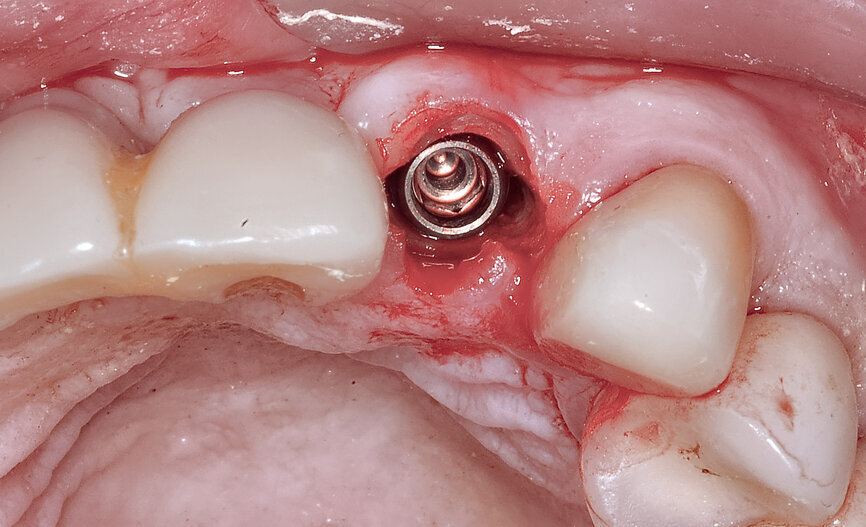

Fig. 23: The implant, seen prior to placement,

using the R2GATE surgical carrier for full-template guidance through the sleeveless guide.

Fig. 24a: Depth control and rotational positioning were accurately

confirmed with the notch indicator on the template corresponding with the insertion tool (a). The occlusal view illustrated that the anti-rotational internal

conical–hexagonal connection was positioned towards the facial aspect (b).

Fig. 25: Using an implant-specific SmartPeg, a baseline ISQ value of 76 confirmed sufficient initial stability to place an immediate restoration.

Fig. 26a: The prefabricated CAD/CAM abutment and transitional crown

Fig. 26b: A post-op periapical radiograph confirmed successful sub-crestal placement of

this platform-switched design.

Fig. 26c: The abutment in place.

Fig. 26d: The soft-tissue contours were excellent; no sutures were required for the transitional restoration.